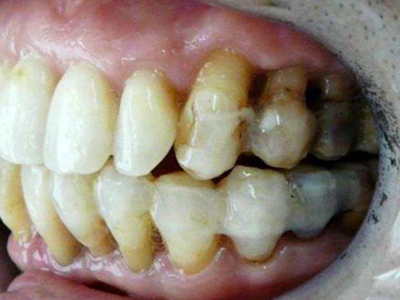

牙龈退缩上排多颗牙的牙根暴露图

牙龈退缩导致上排多颗牙齿的牙龈回缩,部分牙根暴露在外,伴有牙齿松动、口臭等症状,是由于牙周炎、局部受力过大等因素导致。